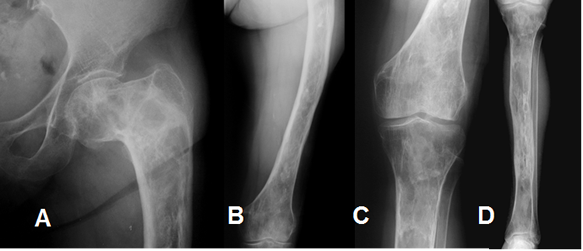

Fig 101. Displasia fibrosa.

Rx AP del miembro inferior izquierdo. Alteración de la densidad en toda la extremidad, por displasia fibrosa poliostótica.